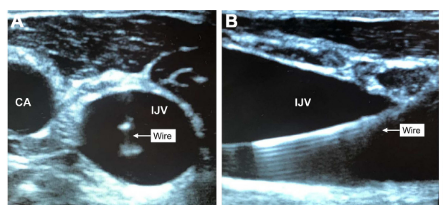

患者相关因素可以通过识别困难的CVC放置的危险因素,并适当地升级到有经验的操作人员,提供适当的镇静药物和适当的位置来减轻。由于有限的通路部位或特定的临床需要(如血液透析导管),导管相关因素可能是不可避免的。环境因素通常是固定的。因此,预防CVC放置机械并发症的最佳可行干预措施是操作员培训和使用程序化和术后确认模式。与有经验丰富的操作者相比,缺乏经验的操作者并发症发生率更高。“经验”的定义在文献中并不一致,最近的一项研究将有限的操作者经验定义为在选定的静脉中放置少于100个CVC,这表明没有经验的操作者发生轻微和重大机械并发症的风险更高。操作员培训应强调限制尝试和考虑替代方法的重要性。当同一操作者进行三次以上的尝试时,机械并发症的发生率会增加6倍。在一项对有经验丰富的操作人员的前瞻性研究中,第二次尝试发生机械并发症的风险是失败的10倍,尝试两次以上机械并发症的可能性是40倍。因此,建议在一次尝试失败后,操作者应采取以下行动之一:(1)换为更有经验的操作者;(2)增加一名辅助人员;(3)优化操作机制;(4)考虑使用替代穿刺点;(5)考虑使用额外的确认方式;或(6)考虑与手术团队合作,如介入放射学或手术。验证是补充步骤,用于提高静脉通路的准确性,减少导管位置不当的发生率和增加安全性。验证性方法可以在CVC放置之前、期间和之后使用。导管尖端的确切位置一直是一个有争议的话题,但通常认为尖端应该平行于中心静脉的长轴,以优化流量和避免潜在的血管壁损伤。上半身CVC的最佳最终导管尖端位置被认为是在SVC的下三分之一处,邻近RA,平行于静脉长轴,在心包反折之外。对于IVC通道,末端应超过髂静脉汇合处。太远的导管可能会导致血管穿孔或RA导致栓塞,而太近的导管可能会增加血栓形成和刺激性药物输注血管损伤的风险。错位的CVC也可能导致不可靠的用药和估计CVP的错误。使用超声有助于目视评估目标静脉和邻近结构之间的关系以及扩张前导线在目标血管中的位置(图a和b)。静态超声使操作者能够在手术准备和覆盖之前确定一个适当的、有足够大小的、没有解剖屏障的静脉血管,包括邻近的动脉。它还可以促进病人的最佳定位,如体位,增加颈静脉或锁骨下静脉的横断面积,或减少颈静脉与颈动脉的重叠。然而,单纯的静态超声可能是不够的;静态超声提高了首次插入的成功率,但对于总体成功率和动脉穿刺率却不确定。因此,在操作过程中使用动态超声增加了首次尝试和整体插管成功率,并显著减少了机械并发症、尝试次数、每次插管时间和无意中的动脉穿刺。